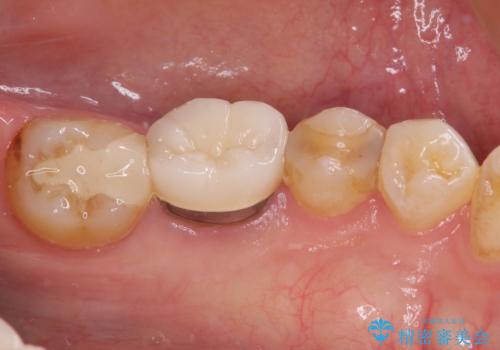

- 冷たいものがしみるとのことで来院された患者様です。

診査を行った結果、第一小臼歯にある樹脂の詰め物(コンポジットレジン)と歯の境目が痛みの原因であることが分かりました。

また、隣接する第二小臼歯も虫歯になっていることも分かったため、2歯を同時に治療するにしました。

下顎の目立つ位置であるため、セラミックインレーによる修復治療を行うこととしました。

精密に型取りを行ったセラミックインレーを装着したことで、治療後にはしみたり痛んだりという症状は治まりました。